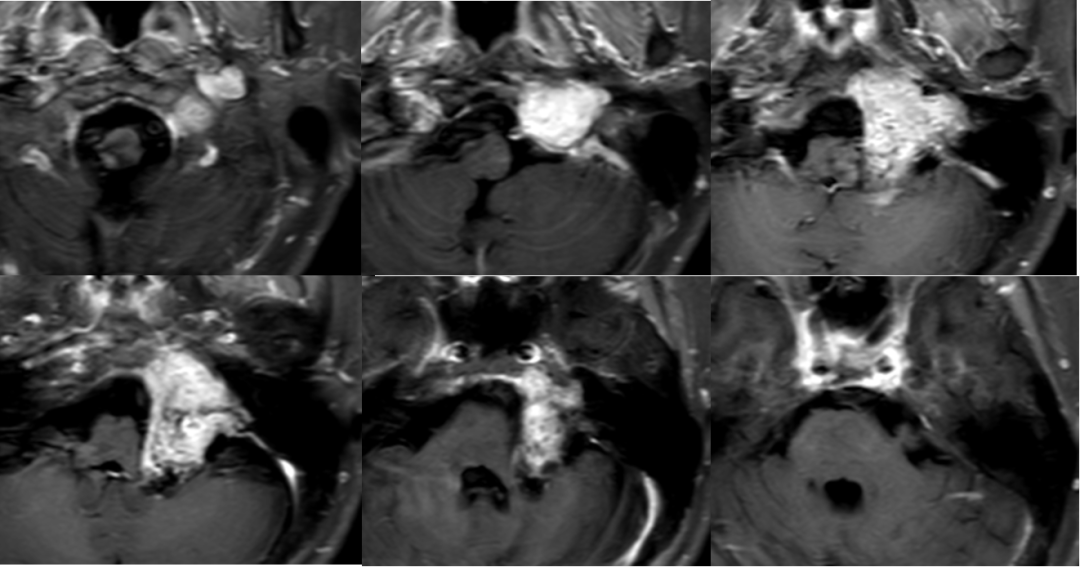

术后影像

![]()